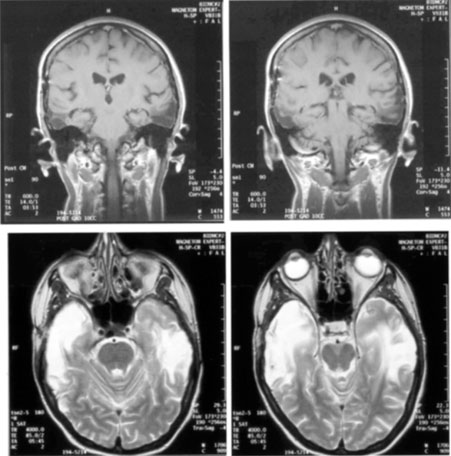

Transient cerebral blindness occurs in about 1% to 15% of patients with pre-eclampsia or eclampsia.97,98,110 Fluctuations in blood pressure with peripartum blood loss may contribute.111 The pathogenesis is analogous to that of hypertensive encephalopathy, with development of petechial hemorrhages and focal edema from impaired cerebral vascular autoregulation, and ischemia from vasospasm.98,112 CT scans may be normal or show bi-occipital lucencies.98,113 MRI is more sensitive, showing T2 hyperintensities and T1 hypointensities similar to those in hypertensive encephalopathy.112,114 Management is that of eclampsia, with magnesium sulfate, fluid restriction, and blood pressure control. The prognosis is good, with virtually all women regaining vision within a few hours to a week, rarely as long as 3 weeks.98